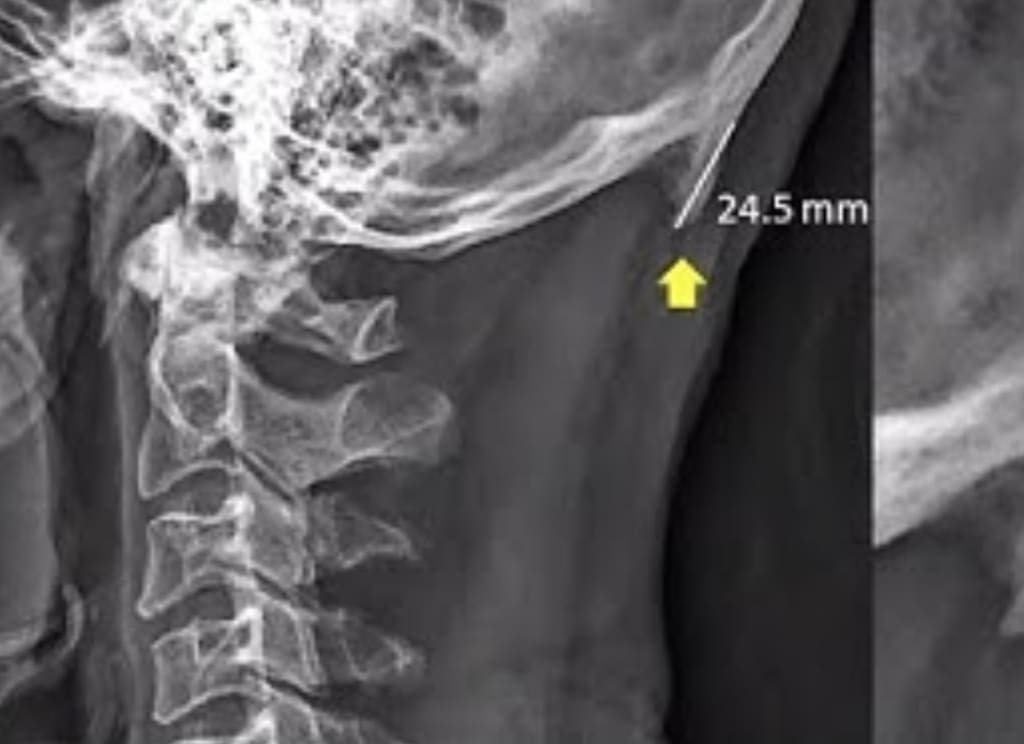

A study was in the Scientific Reports journal a while back that found bony growths on the bases of skulls of around 400 adults, ages 18 to 86.

The idea that cellphones and other modern technology could lead to physical changes in our bodies, such as the growth of bone structures like the external occipital protuberance (EOP) in the skull, has been a topic of discussion in recent years. In a study conducted by David Shahar and Mark Sayers from the University of the Sunshine Coast, they proposed a link between the use of phones and tablets and changes in bone structure.